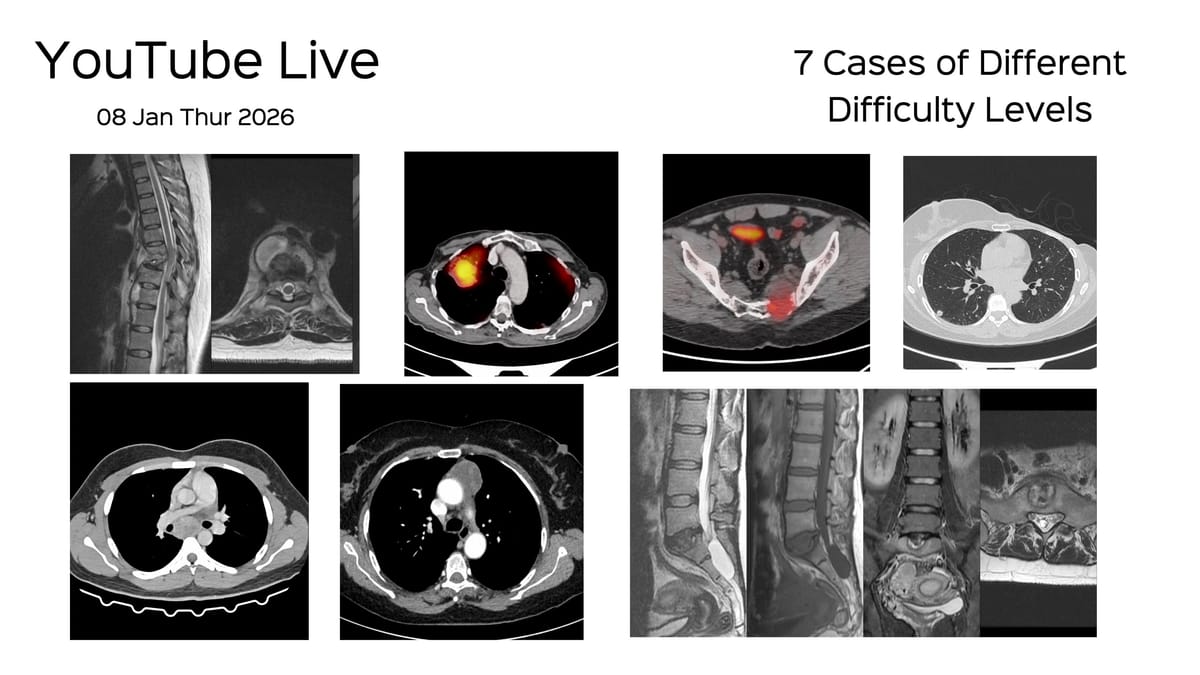

I will be discussing these 7 biopsy cases from Dec 2025, across different levels of difficulty.

Here is a video of the 7 cases that I am going to discuss.

7 cases of different levels of difficulty discussed live on 08 Jan 2026